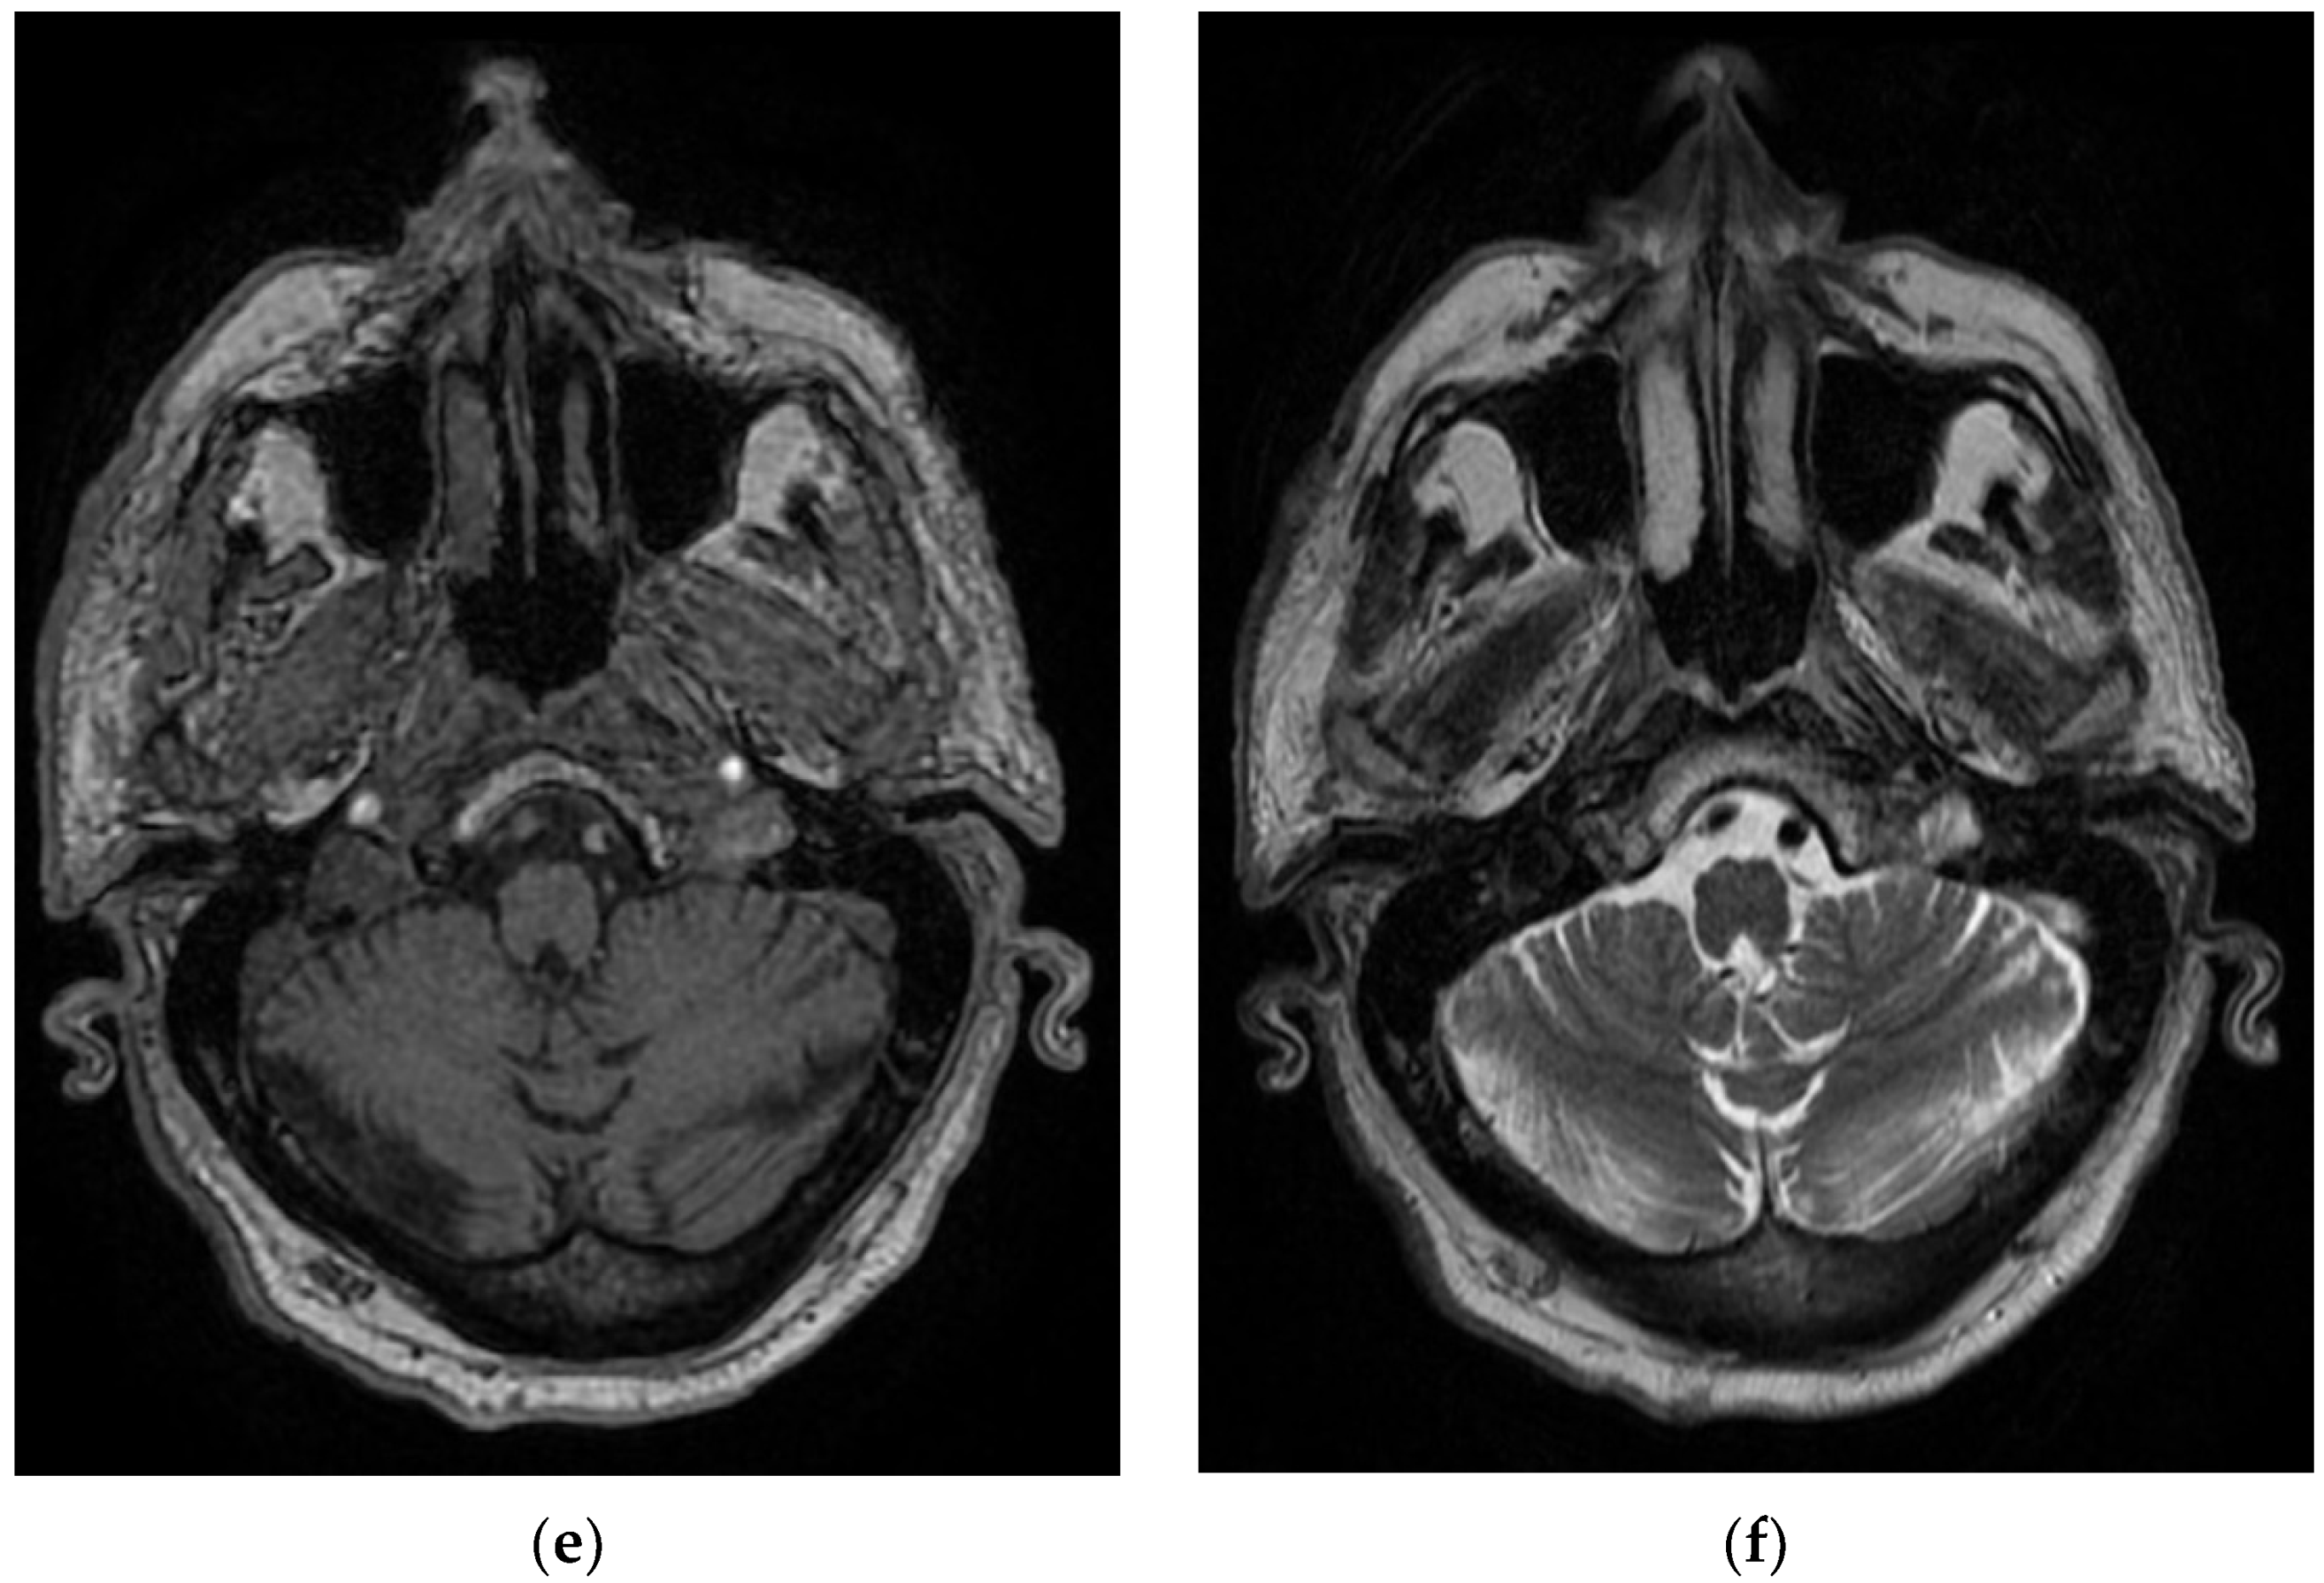

This patient, aged 66 years, presented to the emergency department for language disorders with fluctuating evolution. Neurological objective examination on admission showed the patient to be conscious, cooperative, with no motor deficits, lower limb ataxia, and bilateral plantar–indifferent cutaneous reflex. During hospitalization, he underwent a diabetes consultation, after which insulin therapy was initiated, a carotid Doppler echo, showing bilateral carotid atheromatosis, an EMG, which showed predominantly sensory axonal polyneuropathy, a cervical–thoracic spine MRI which showed T7–T9–T10 intraspongious herniation and a C5–C6 disc overhang; there was also a C6–C7 protrusion with left C7 radicular conflict, and a brain MRI evidencing T1–T2 nonhomogeneous hyperintense material partially occupying the transverse sinus and left–sided sigmoid sinus, with extension to the jugular bulb–left transverse–sigmoid–jugular venous subacute thrombosis (Figure 6).

Figure 6. Hyperintense and nonhomogeneous T1 and T2 material, in the Case 6 patient, which partially occupies the transverse sinus (a,b) and left sigmoid sinus (c,d) towards the jugular bulb (e,f)–left venous transverse–sigmoid–jugular subacute thrombosis.